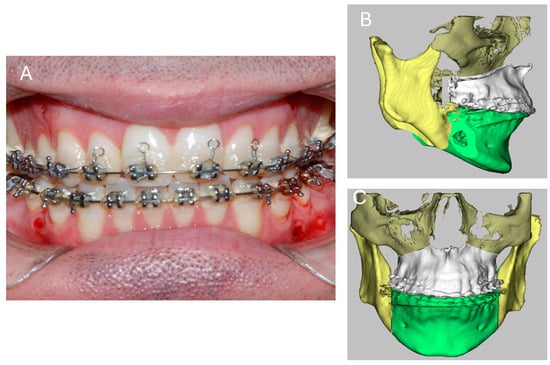

2.1. Surgical Procedures

2.2. Bilateral Sagittal Split Osteotomy (BSSO)

4.2. Advantages of Wedge Osteotomy